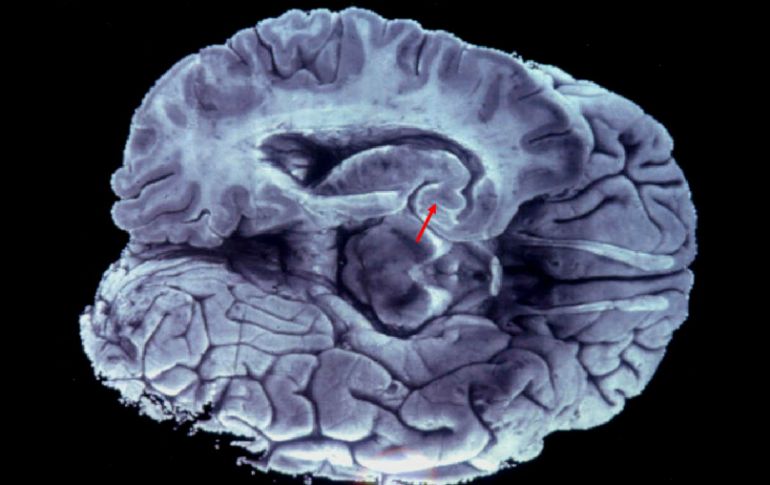

La temperatura influye en la calidad del aire y el riesgo de sufrir un enfermedad cerebrovascular. EFE / ARCHIVO